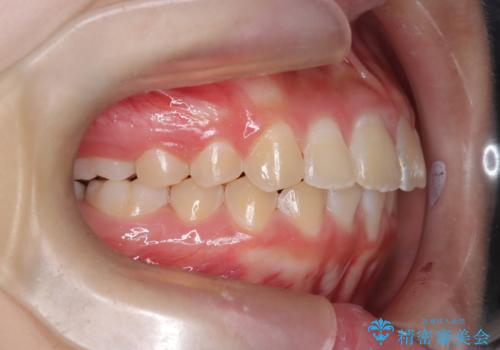

- 前歯が出ていることを主訴に来院されました。

インビザラインにて奥歯の遠心移動を行いながら最大限前歯が下がるように治療を行いました。

今回は遠心移動とIPRによってここまで前歯を下げることができました。